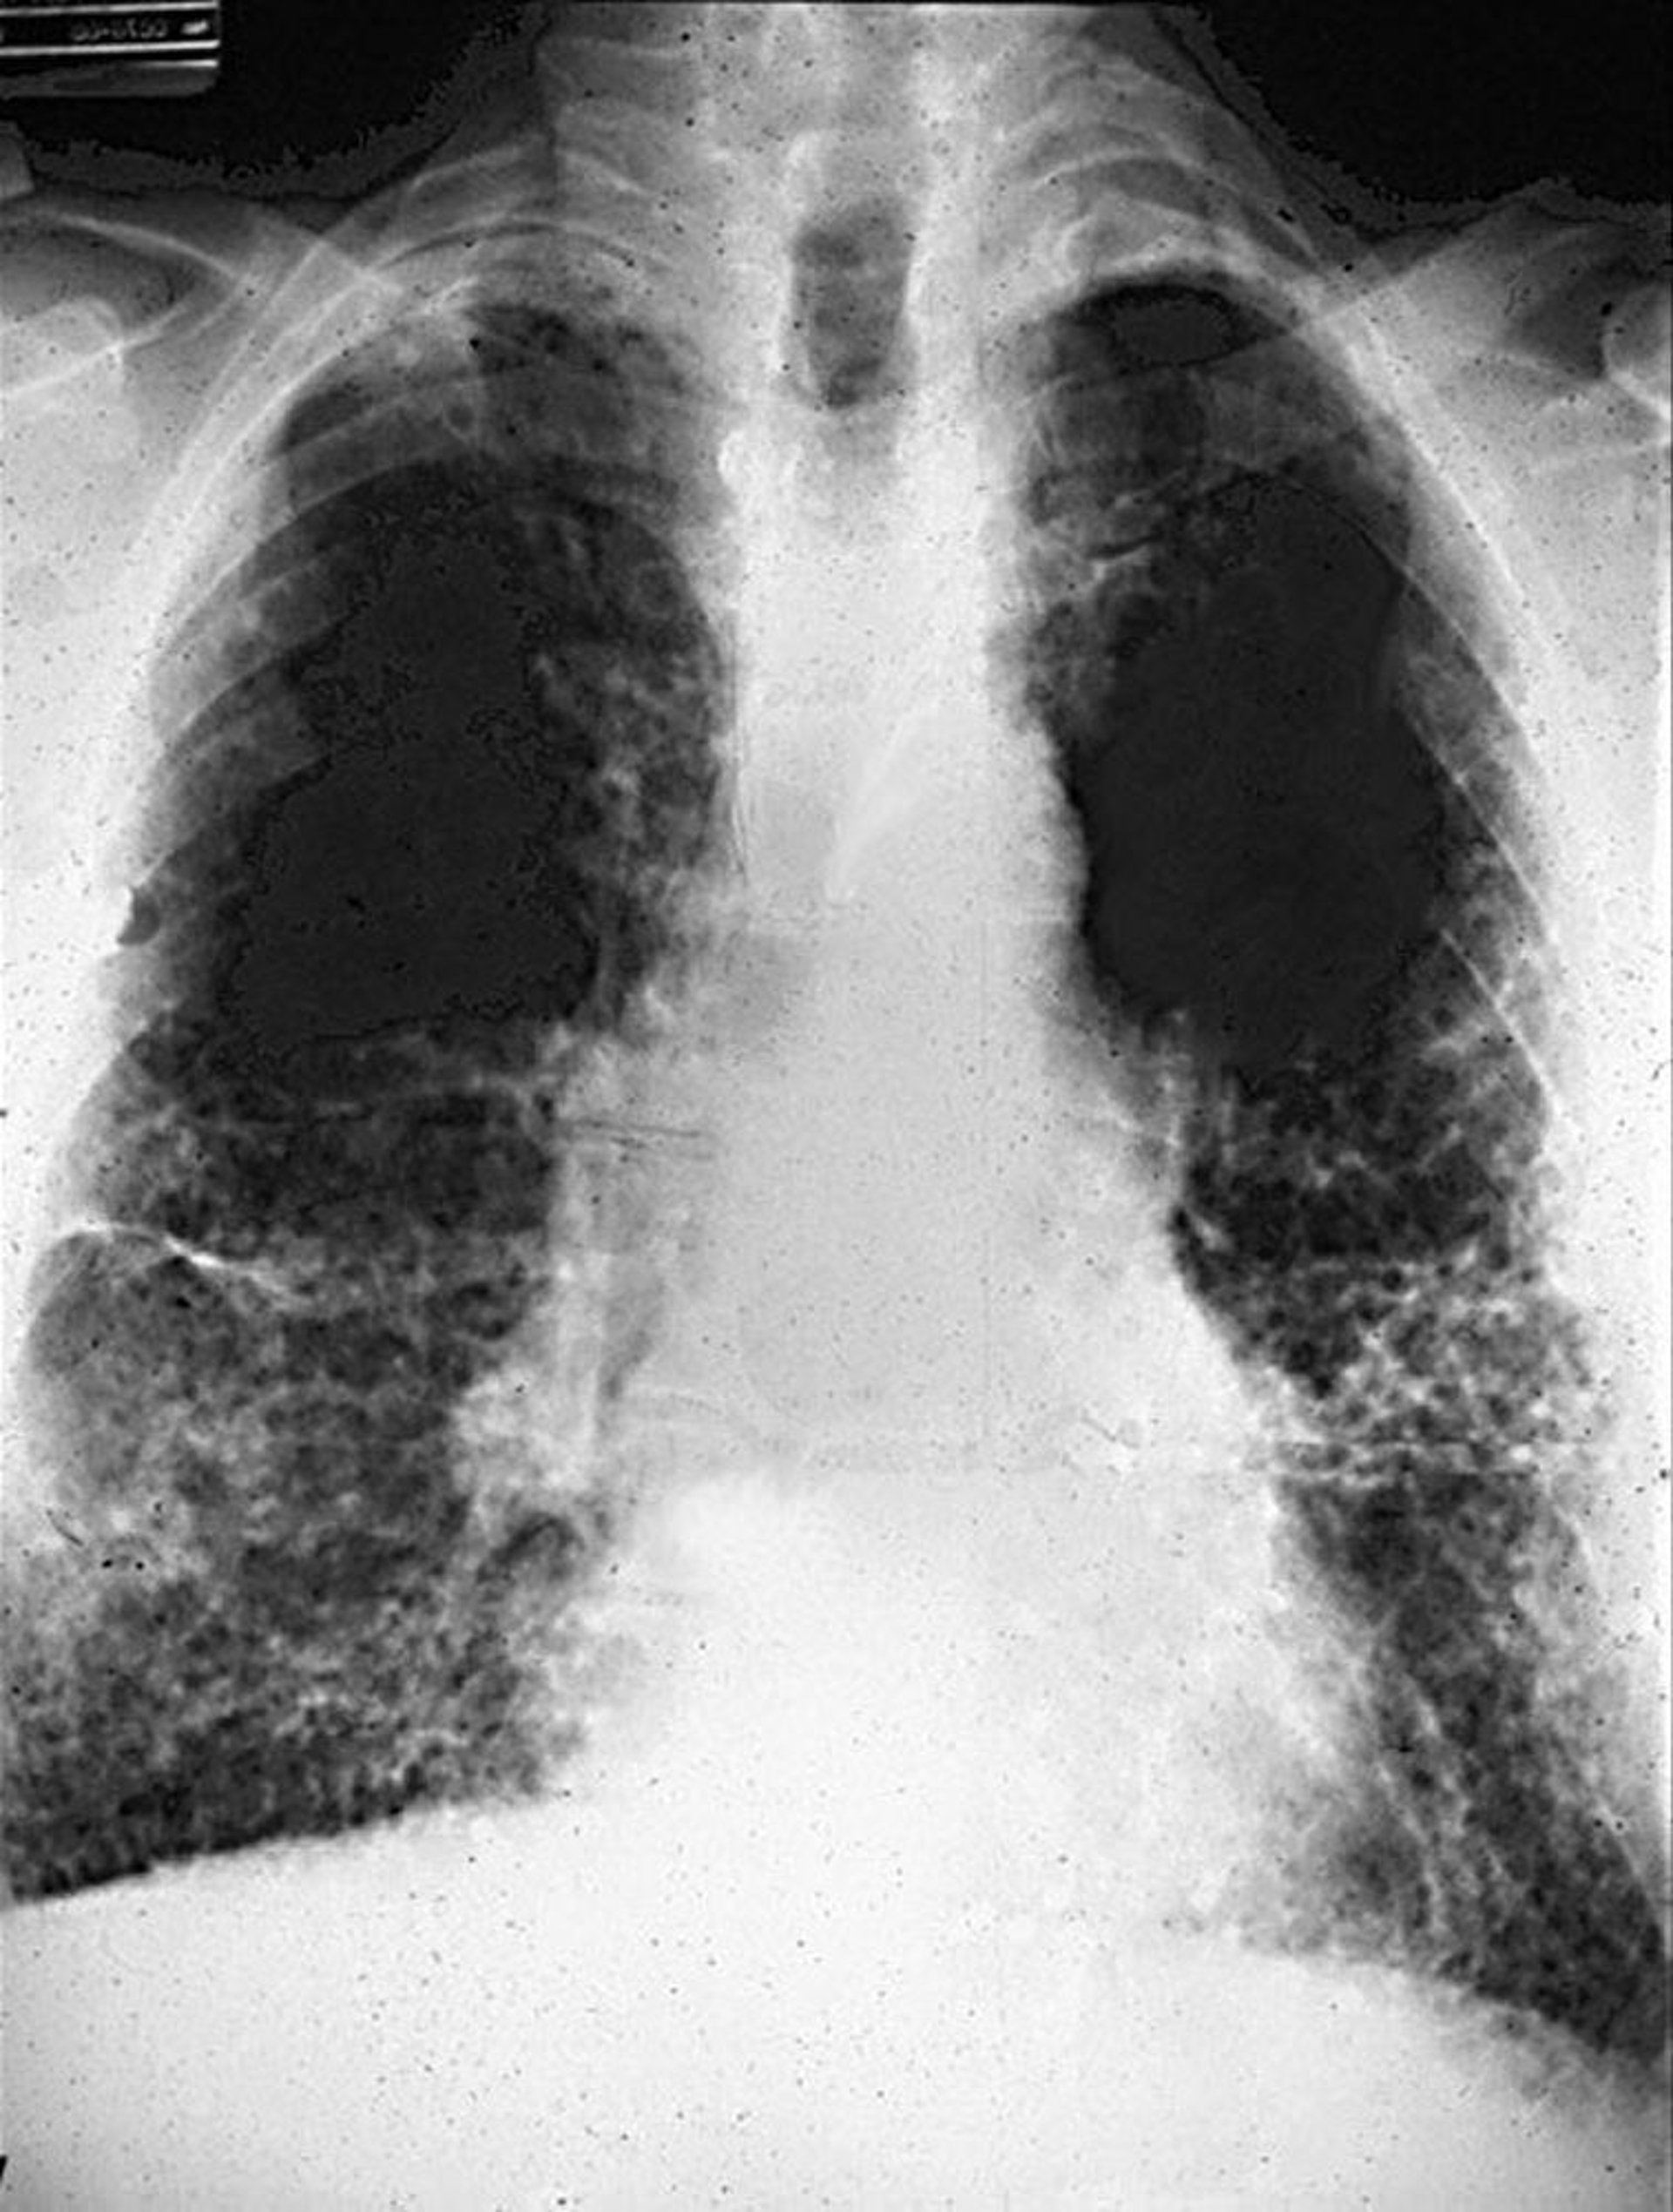

Der Röntgenthorax zeigt bilaterale, lineare retikuläre Trübungen, die eine Fibrose anzeigen, in der Regel in den peripheren Unterlappen, mit oder ohne pleurale Veränderungen. Die Thorax-CT bietet eine höhere Sensitivität bei der Erkennung von Anomalien des Pleuras und des Parenchyms und zeigt in der Regel ein übliches interstitielles Pneumoniemuster der Lungenfibrose. Wabenbildung, die das mittlere und untere Lungenfeld betreffen kann, zeigt eine fortgeschrittenere Erkrankung an.

The International Labour Organization system (International Classification of Radiographs of Pneumoconioses) wird verwendet, um das Vorhandensein und den Schweregrad von Pneumokoniosen basierend auf Größe, Form, Lage und Überfluss von Trübungen zu charakterisieren. Eine Asbestose führt zu retikulären Trübungen mit einem Überwiegen der Unterlappen. Lymphadenopathie von Hilus und Mediastinum und noduläre Zeichnung sind untypisch und legen andere Erkrankungen nahe.

Retikuläre Veränderungen mit Honigwabenbildung bei Asbestose.

Image courtesy of David W. Cugell, MD.